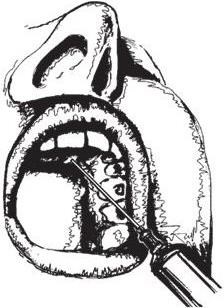

Рис. 1.3. Анестезия подглазничного нерва:

а – внеротовой доступ; б – внутриротовой доступ

Внеротовой доступ: пальпаторно определяют нижний край глазницы, обнаруживают желобок, соответствующий месту соединения скуловой кости со скуловым отростком челюсти и, растянув кожу между1и2пальцами левой руки, вкалывают иглу, отступя на 0,7 см вниз от края глазницы. Иглу продвигают вверх и кнаружи по направлению к кости. Достигнув ее поверхности, не проникая иглой в канал, выпускают анестезирующий раствор. Обезболивание наступает через 2 – 3 мин (рис. 1.3, а).

Внутриротовой доступ: 1 и 2 пальцами левой руки отводят верхнюю губу кверху и кнаружи, а средним пальцем фиксируют место проекции нижнеглазничного отверстия, которое при внутриротовом доступе находится на пересечении двух линий – горизонтальной, проходящей на 0,5 – 0,75 см ниже нижнеглазничного края, и вертикальной, проходящей по оси второго верхнего премоляра соответствующей стороны. Иглу вкалывают на 0,5 см кверху от края прикрепления переходной складки между средним и боковым резцами и продвигают ее вверх, вперед и кнаружи по направлению к нижнеглазничному отверстию до упора в поверхность кости, где и инъецируют анестетик (см. рис. 1.3, б).